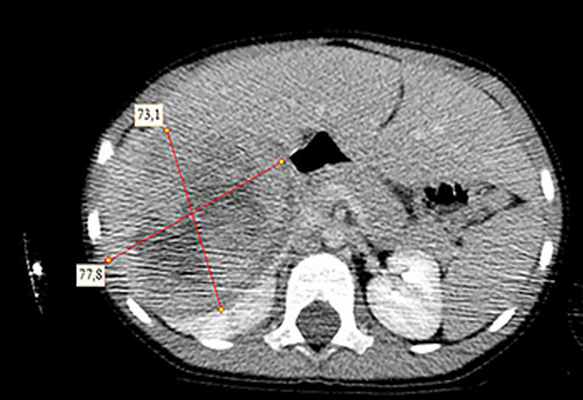

Рисунок 3. Контрольная КТ: опухоль после предоперационной химиотерапии. Ребенку проведена предоперационная химиотерапия. На 5-й неделе лечения КТ-контроль показал уменьшение опухоли в размерах до 90ґ80ґ100 мм (см. рис. 3).

Выполнена операция: лапаротомия, удаление опухоли правой почки с ее резекцией. Гистологическое заключение: классическая нефробластома, промежуточная группа риска (см. рис. 4).